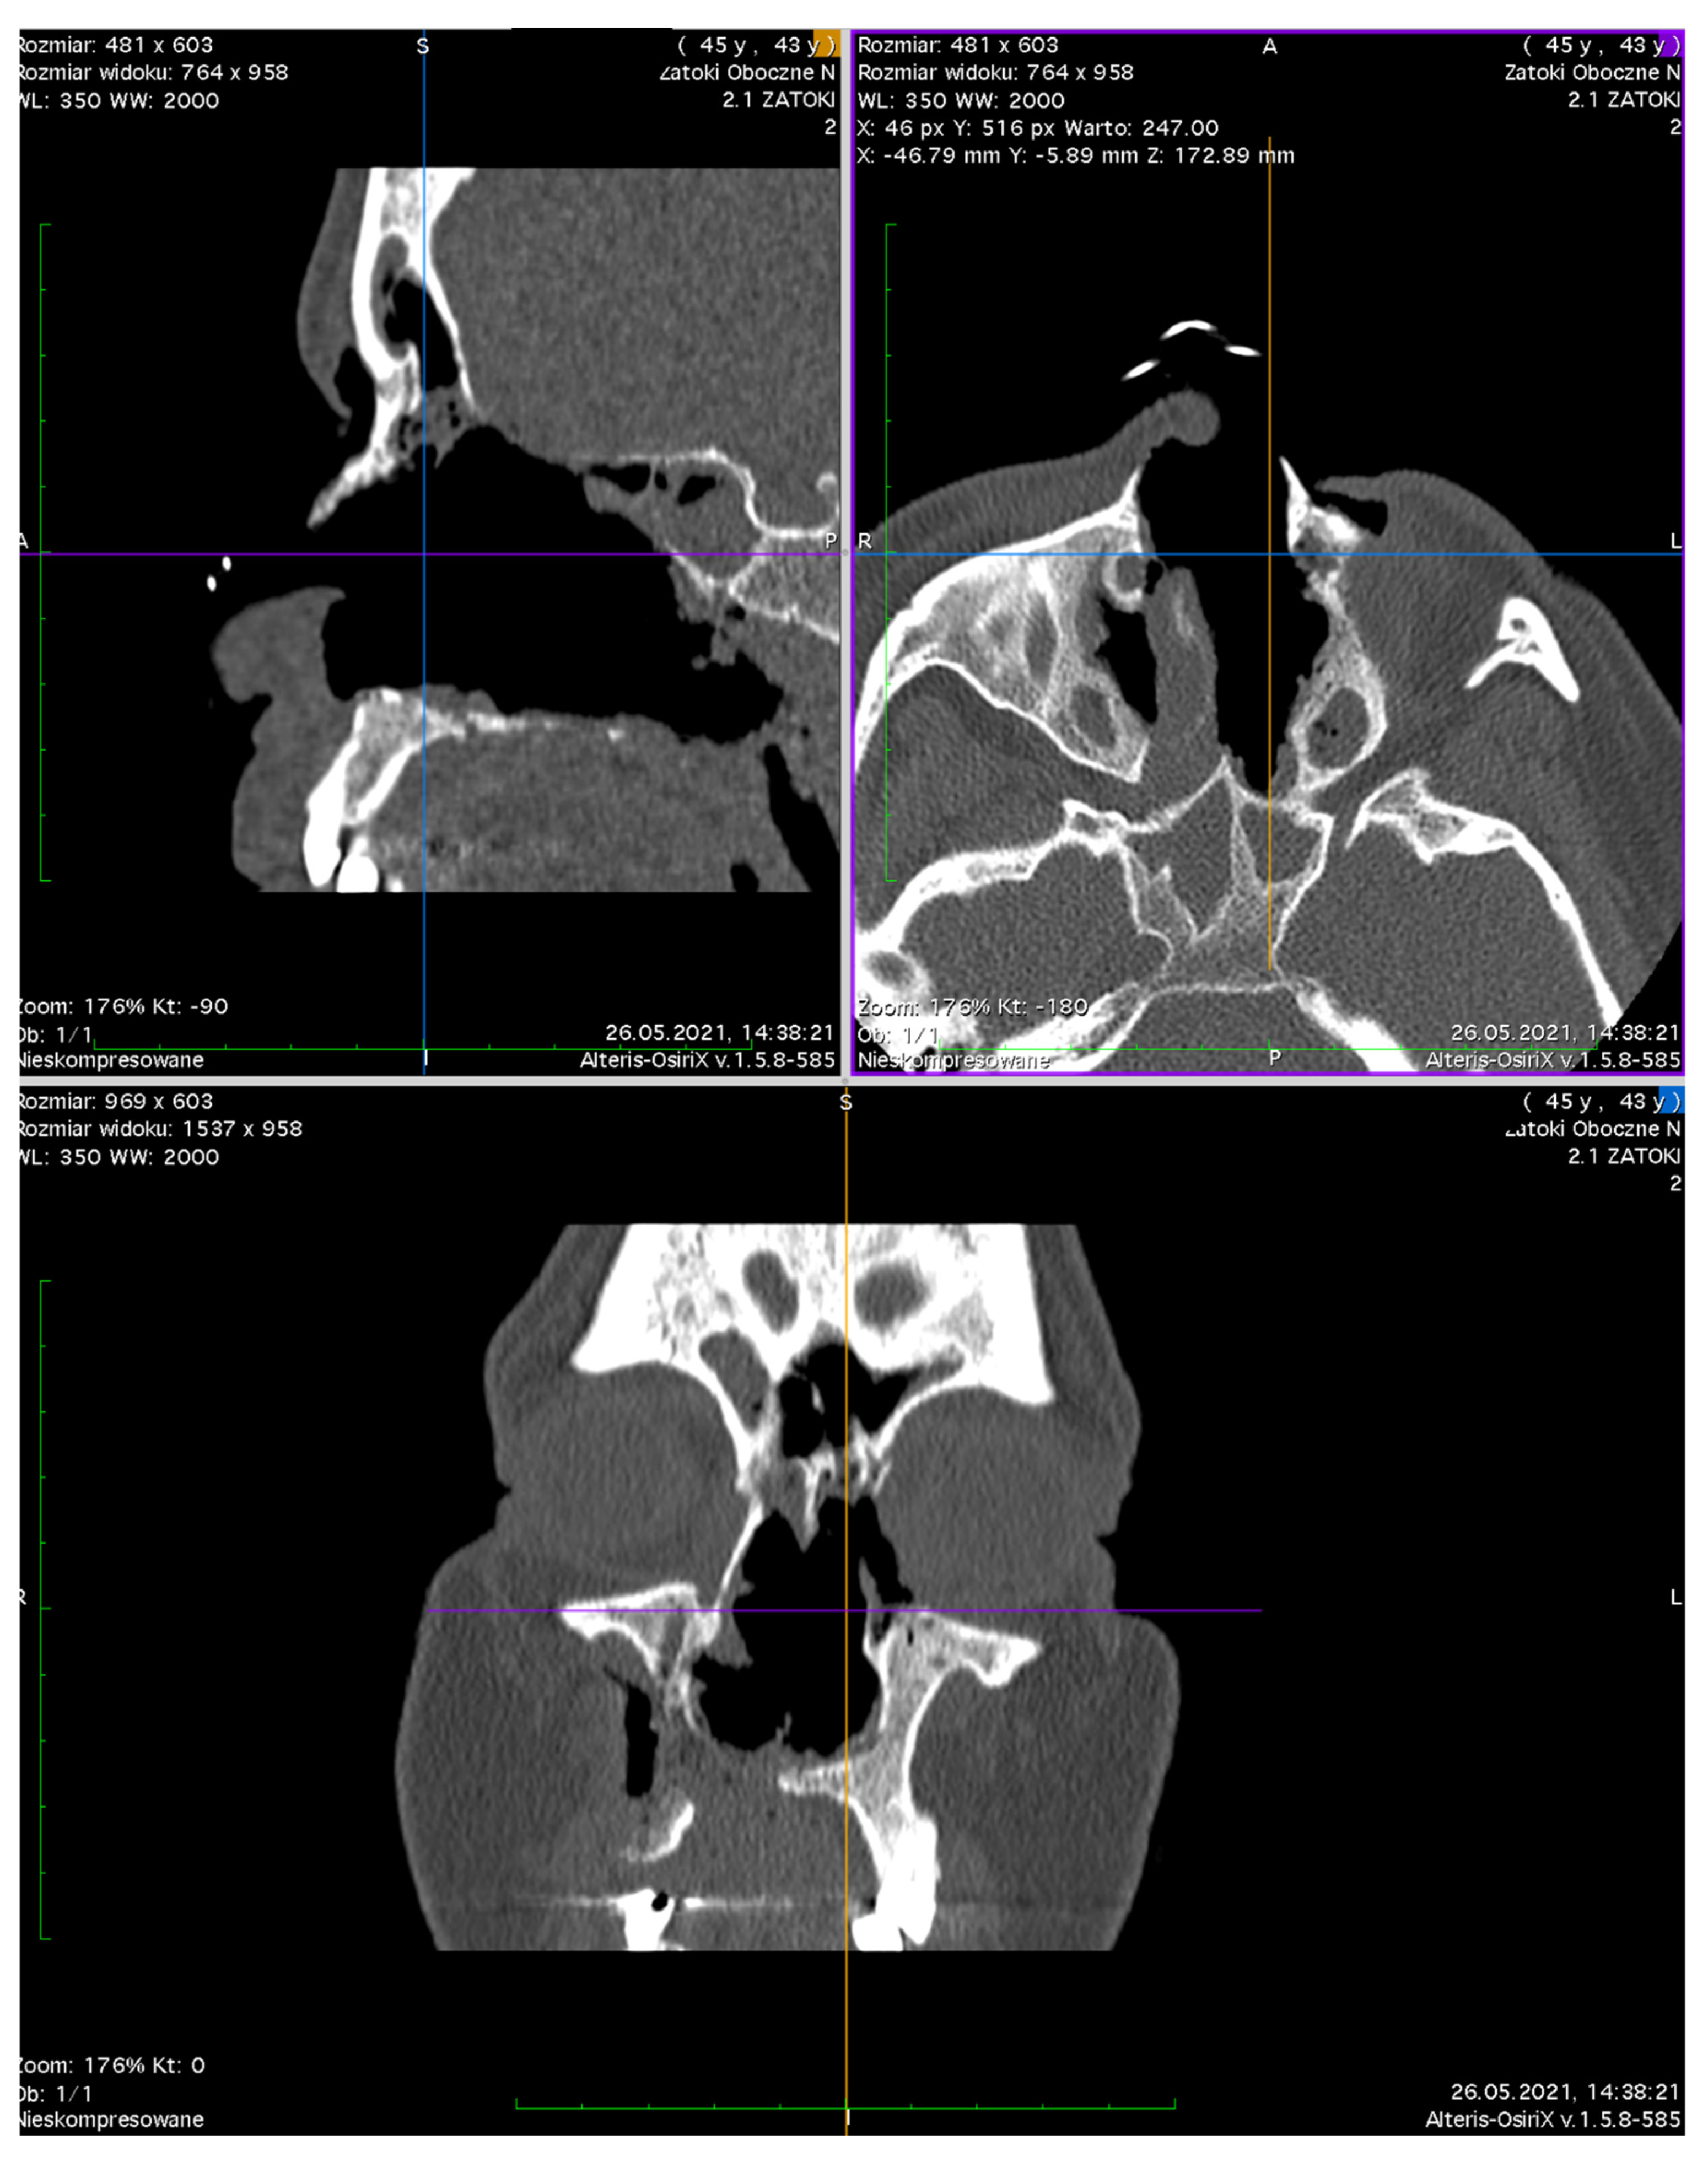

Computed Tomography (CT) of the orbit (Figure 7) revealed the destruction of the medial orbital wall with an inflammatory involvement of the medial rectus and inferior rectus muscles with the limitation of fat tissue in the orbit. The sinuses were open, communicating with the nasal cavity. From the clinical point of view, the structures of the orbit were seen through the nose, the muscles were bare, and the medial part of the orbit was not covered with any tissue; no conjunctiva was present (Figure 8 and Figure 9).

Figure 7. A CT scan of the head. Loss of bony and soft tissue in the middle face and left orbital walls.